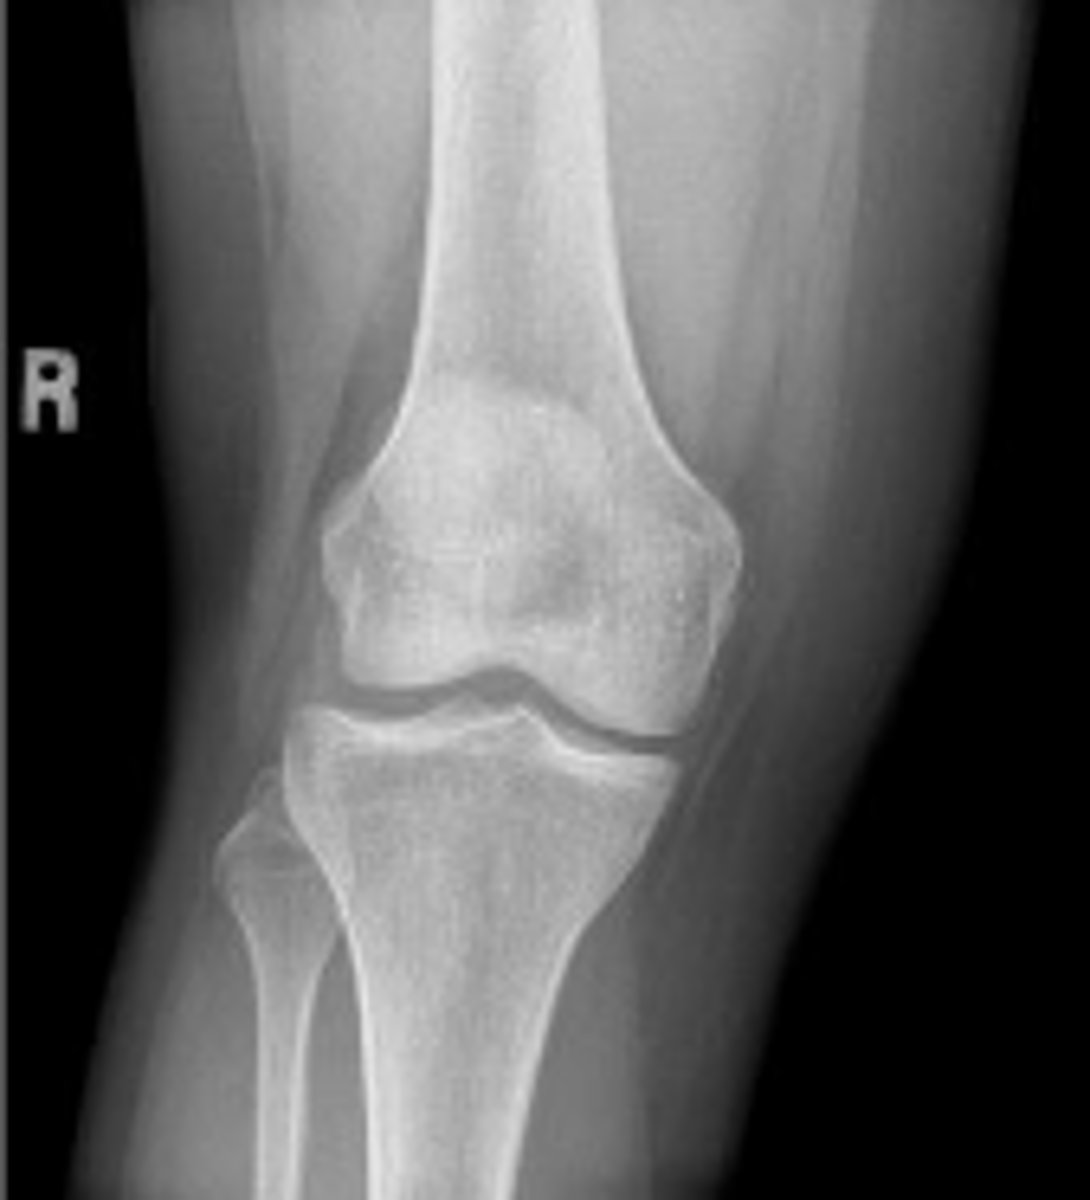

Right AP knee

What is the name of the radiographic view?